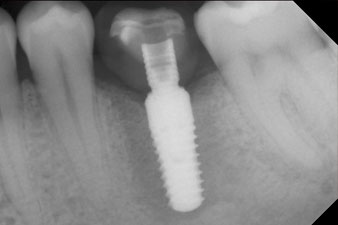

Les dernières photos montrent la couronne composite monolithique retenue par une vis une fois mise en place et la radio de contrôle (Fig. 9 et 10) (6).